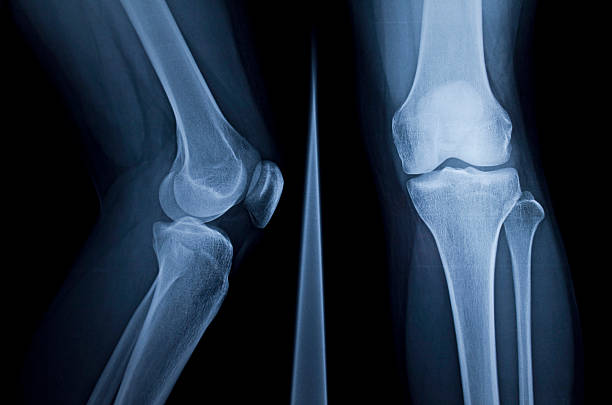

무릎 연골판 손상을 진단하기 위해서는 주로 MRI 검사가 사용됩니다. X-레이 검사는 뼈 위주로 나오기 때문에 연골 손상을 정확하게 확인하기 어렵습니다.